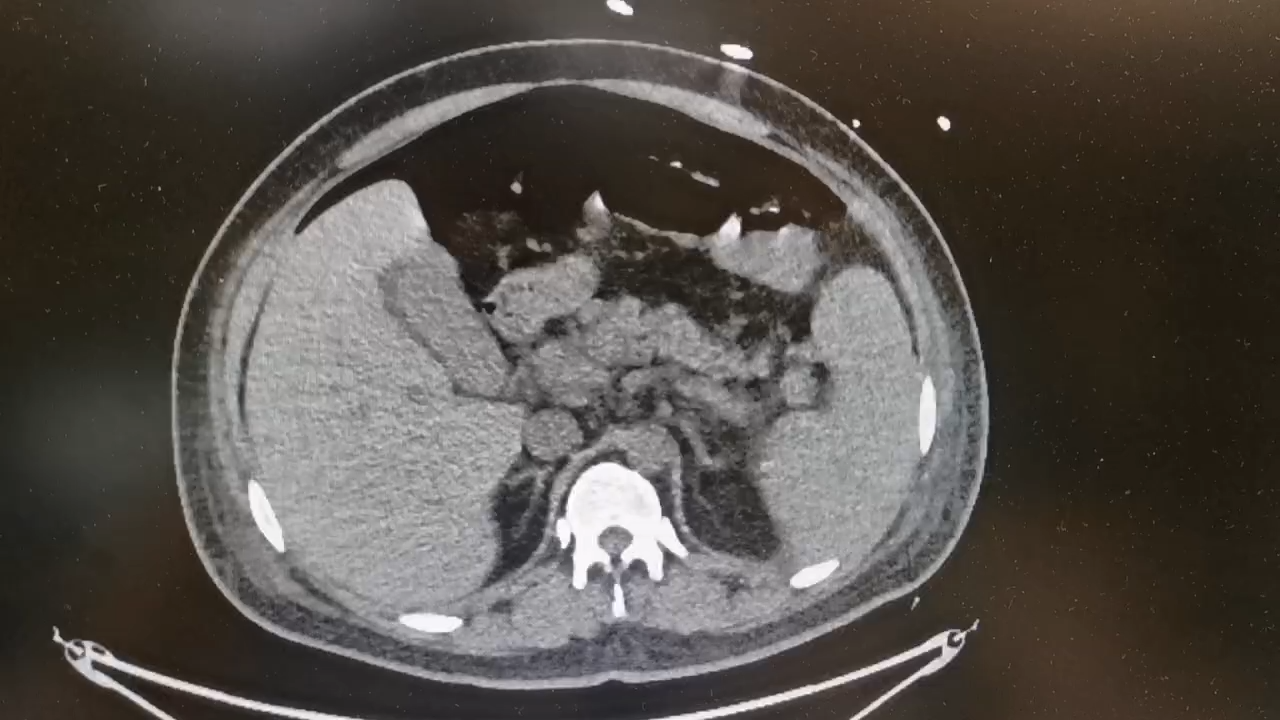

患者入院前12天无明显诱因出现腹泻,稀水样棕褐色大便,4-6次/天,伴乏力,无腹痛、恶心、呕吐,无胸痛、胸闷、憋喘,无发热、咳嗽、咳痰,未行治疗。1天前其同事发现患者没上班、电话不接,遂到宿舍发现其意识模糊,可叫醒,体温:40℃,有大小便失禁,无呕吐,就诊于当地医院行胸腹CT检查:双肺炎症,心腔内低密度灶,脂肪肝,部分肠管扩张并气液平(片子就表现为心衰肺门周围阴影);血常规:血红蛋白43g/L,PCT:2.5ng/ml,总胆红素:47.8umol/L。给予退热、补液等治疗,患者家属为进一步治疗当天转入我院急诊,复查血常规:血红蛋白:42,血小板:121,前降钙素:3.2ng/ml,N端脑钠肽前体:1165pg/ml,D-二聚体:1.5,高敏肌钙蛋白I:686.74ng/L,总胆红素:52umol/L,未结合胆红素:29umol/L。给予纠正心衰、抗感染等治疗后,转入科室。

06-28患者已无任何不适,可以出去做检查了,去复查胸腹CT:

带着病人回病房后,一看片子,影像科老师说,捋了一遍没找到破口,再领着病人回CT室扫个盆部吧!